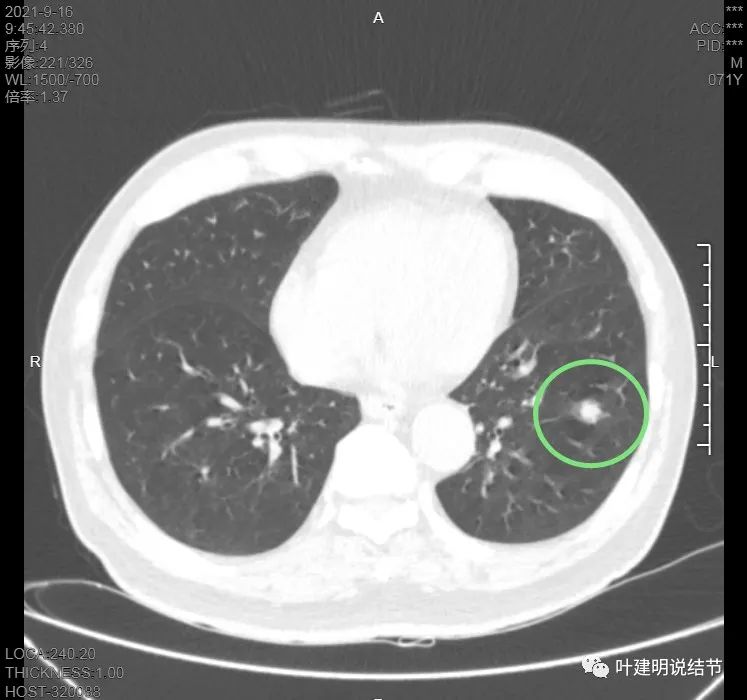

上图见主病灶长方形,边缘平直且光滑,没有毛刺、分叶或胸膜牵拉,粉色箭头示小病灶,在主病灶边上

上图示主病灶边缘非常光滑,膨胀性不明显

上图似乎边缘有点磨玻璃,但这可能是病灶横断面扫到组织相对较少或较薄的地方,其实并不是磨玻璃成分

上图是病灶下缘的样子

这样的病灶应该是良性可能性大的多,纵隔窗上又是如何的呢?